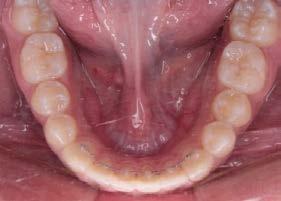

Manejo interceptivo de maloclusión clase II esqueletal

Manejo interceptivo de maloclusión clase II esqueletal con remanente de crecimiento: reporte de un caso clínico

Introducción: La maloclusión clase II provoca proporciones irregulares en el perfil facial. Puede deberse a un maxilar adelantado y a incisivos superiores proinclinados y protruidos. Esta condición puede corregirse mediante el uso de aparatos ortopédicos en pacientes en crecimiento.

Objetivos: Conseguir clase I canina, controlar el crecimiento vertical, disminuir la convexidad esqueletal, reducir la sobremordida horizontal y mejorar el perfil facial. Caso clínico: Paciente femenina de 9 años, clase II esqueletal, biotipo dolicofacial, perfil convexo, clase II molar, clase II canina y proinclinación de incisivos superiores e inferiores. Resultados: Se logró clase I canina, se controló el crecimiento vertical, se redujo la convexidad esqueletal, se mejoró la sobremordida horizontal y el perfil facial. Conclusiones: El uso combinado de aparatos ortopédicos y aparatología fija en pacientes en crecimiento, junto con un diagnóstico y plan de tratamiento acertado, permite obtener resultados exitosos y estables en la corrección de estas maloclusiones.

Palabras clave: arco extraoral, clase II, ortopedia, cantilever, crecimiento.